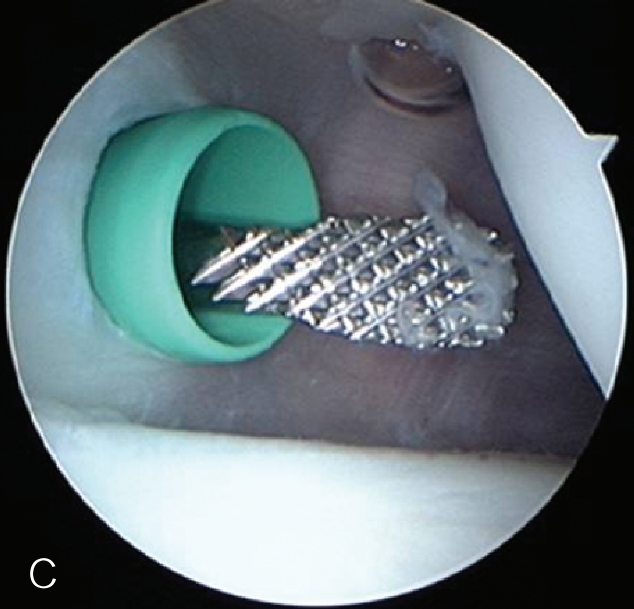

上盂唇修复

创建前方和后方入路时,与关节盂面成恰当角度,以便锚钉的置入。 高位和外侧放置前方入路可以有效地进行单纯上盂唇的修复。该入路位于肩袖间隙的高位和外侧,用腰椎穿刺针进行定位。非刚性套管有助于在肱二头肌腱附着部后方置入锚钉。 可用于 SLAP 修复的辅助入路包括 Wilmington 入路(肩峰后外侧角前方、外侧各 1 cm 处)或 Neviaser 入路(锁骨、肩峰、肩胛冈组成的三角形内,肩峰内侧 1 cm 处)。

B. 应首先用腰椎穿刺针确定辅助入路的恰当位置和方向。然后在皮肤上做一个小切 A B 口,钻头导向器置入关节。